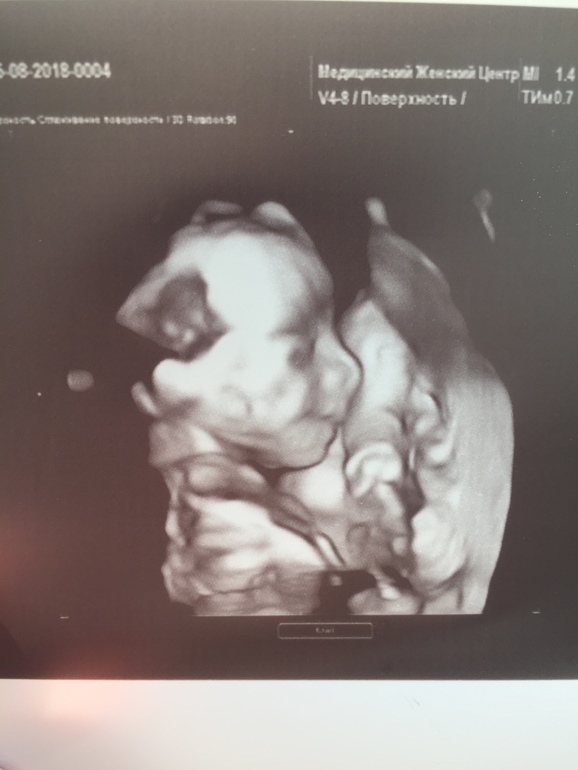

23 неделя

Была на узи и куча вопросов. Болит низ живота